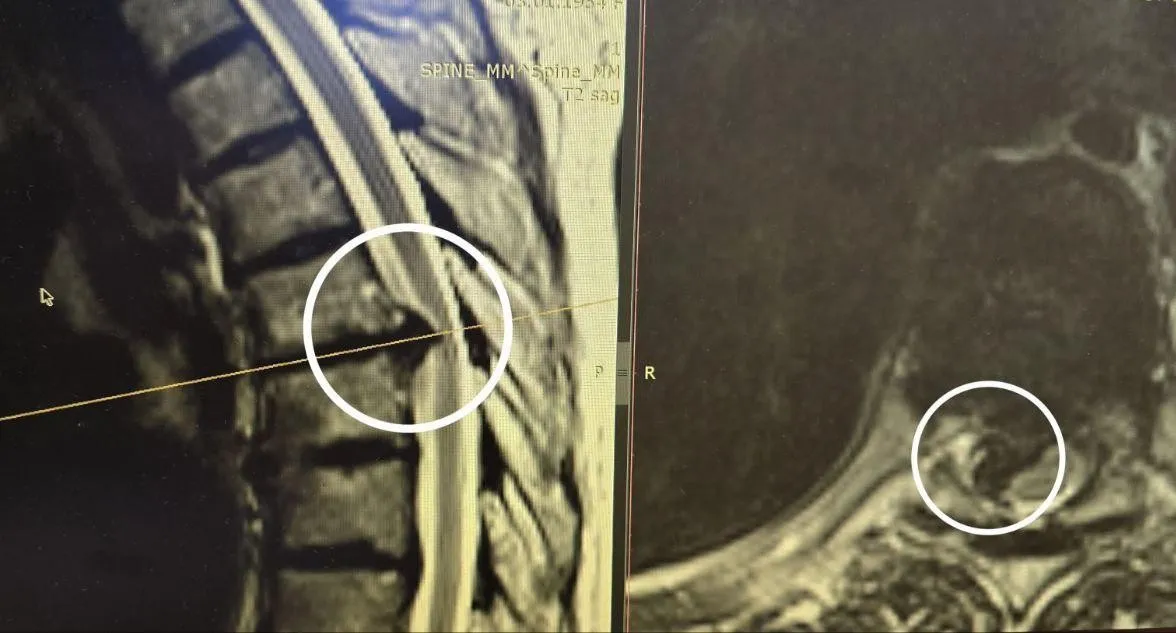

По словам заведующего отделением нейрохирургии Павла Савинкова, грыжа была настолько твердой, что ее текстура напоминала камень. Она проросла в спинномозговой канал, почти полностью перекрыв нервные проводники. Операция длилась несколько часов, и хирургам пришлось использовать алмазный бор, чтобы аккуратно удалить грыжу.

К счастью операция прошла успешно. Уже на следующий день после операции пациентка встала на ноги, боли в спине исчезли, а сила в ногах вернулась. Контрольные исследования показали, что сохранившиеся нервные проводники восстановили свою функцию. Сейчас женщина уже выписана из больницы.